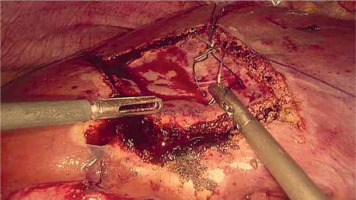

Ultrasonic devices (Photo 7), designed to dissect selectively liver parenchyma utilizing mechanical waves, preserving small vessels and bile ducts and sucking crushed liver parenchyma at the same time, maintain a dry operative field [41]. Therefore, ultrasonic devices are essential in major liver surgery.